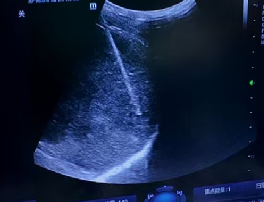

超声示:肝右叶片状稍高回声区,结合病史考虑术后改变。

经过三位重建,评估肿瘤体积缩小,肝左叶体积增大,全身PET-CT评估门脉癌栓没有活性,与家属充分沟通病情后决定行手术切除。